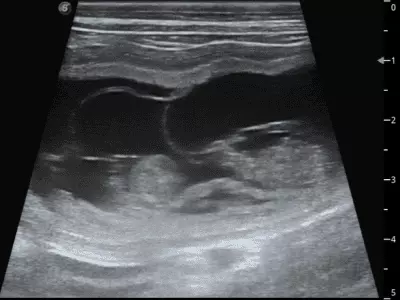

W tym wydaniu m.in: problemy trawienne, dermatozy psychogenne psów, przepuklina brzuszna pępkowa zewnętrzna, szpiczak mnogi, starszy pies z objawami krwioplucia, przegląd objawów behawioralnych w kontekście różnych chorób.